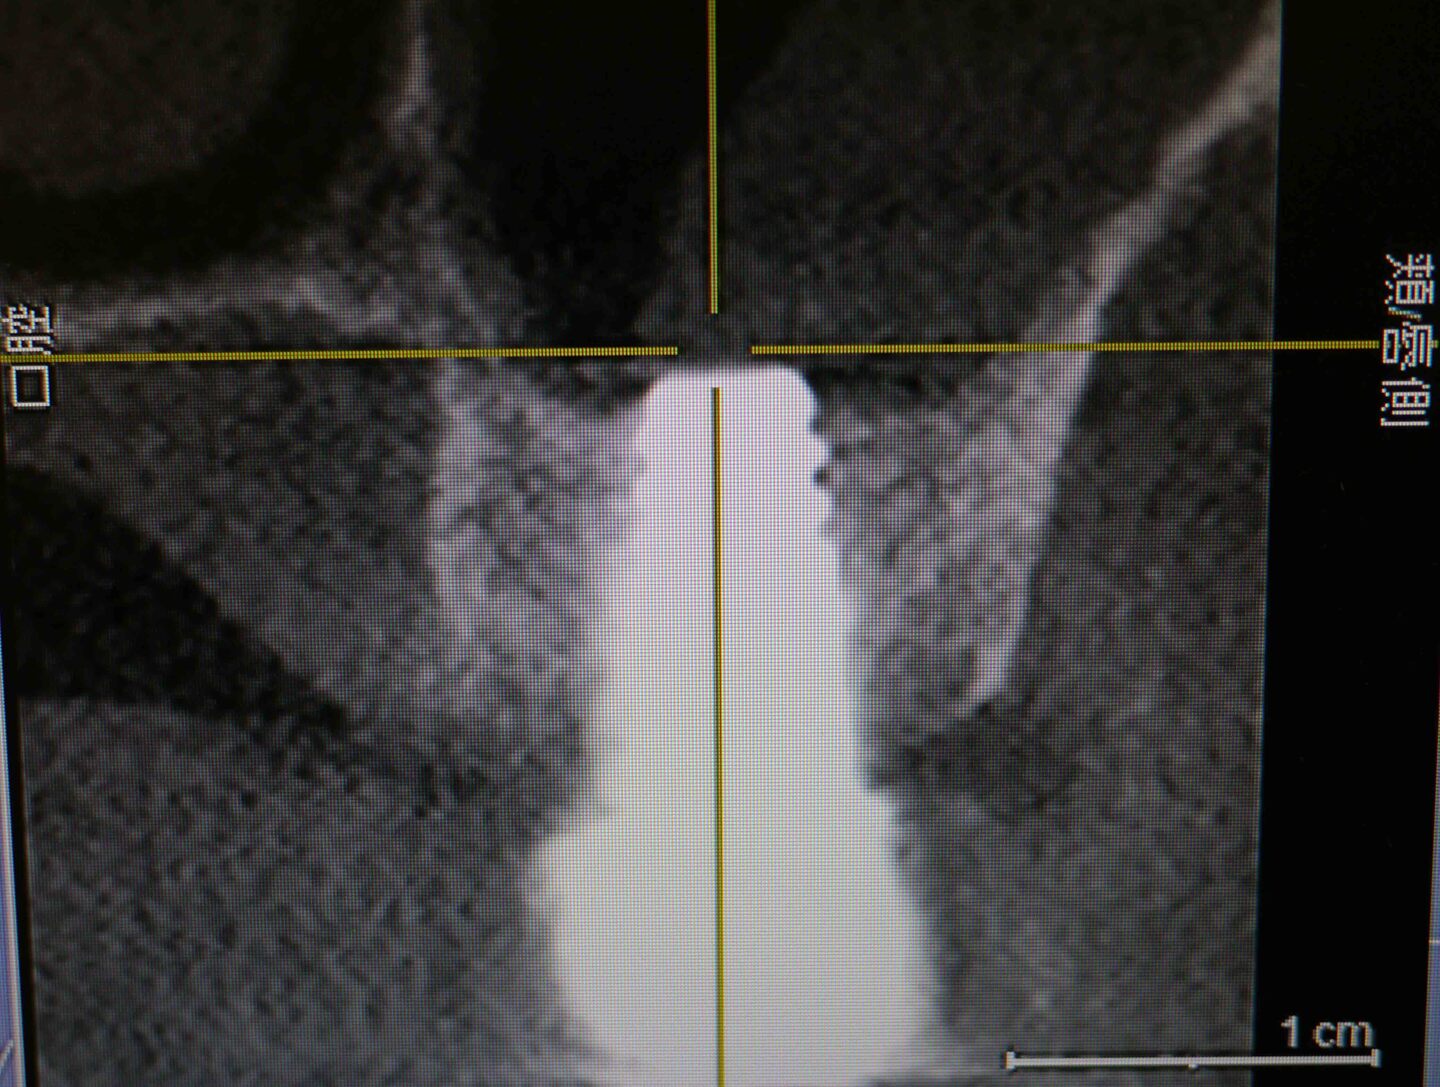

CT画像 2

右上7番埋入予定の骨を後側から見たCT画像